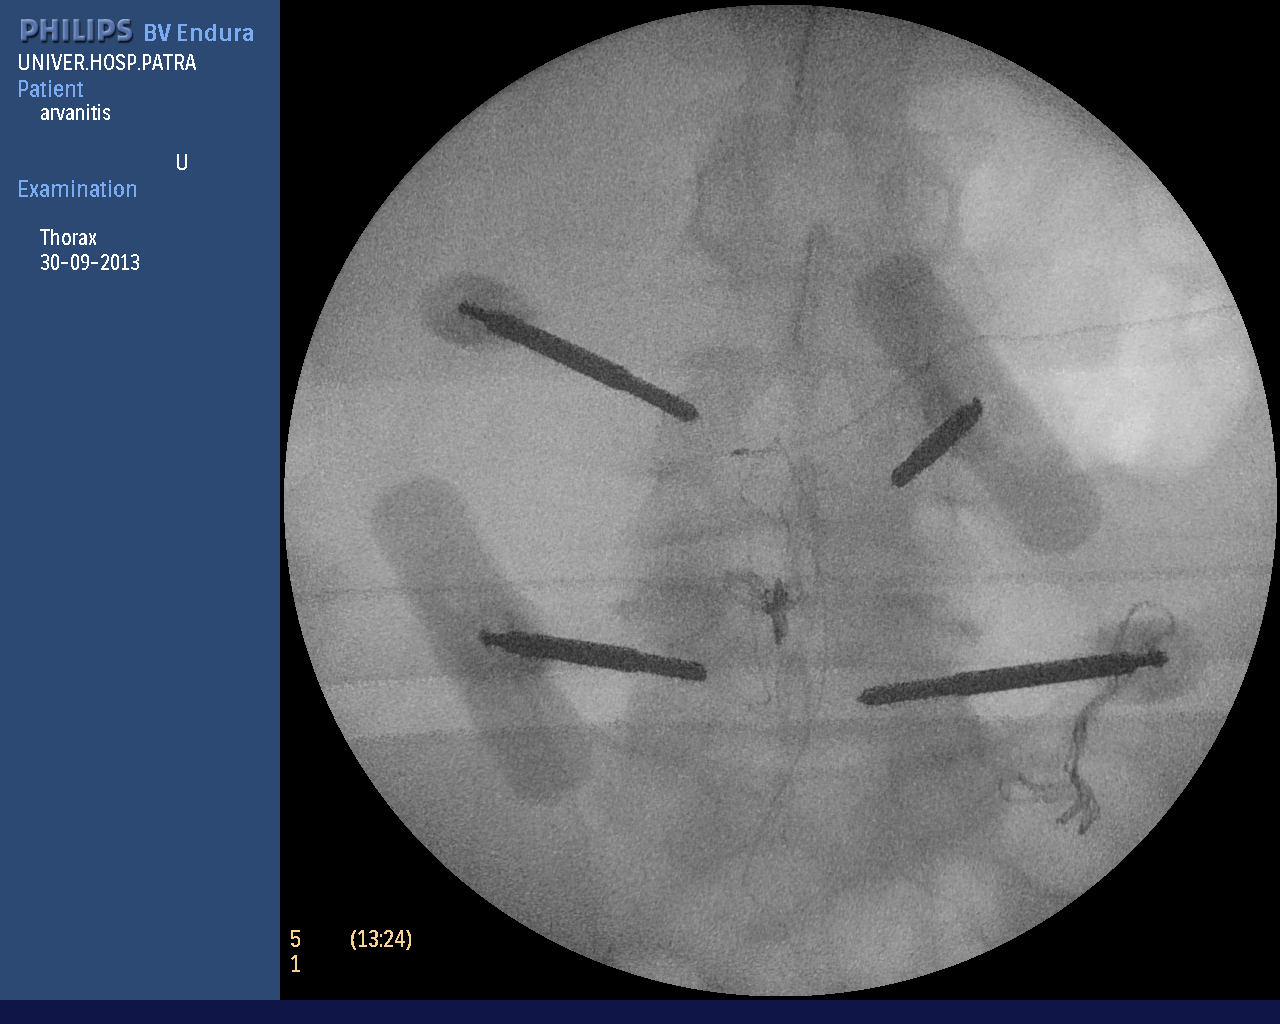

In more complex spinal problems (vertebral fractures, spondylolisthesis, instability, etc.), spinal fusion is needed, i.e. the placement of special screws and rods to stabilize the vertebrae. The operation is also performed percutaneously, avoiding tissue injury and postoperative pain. As shown in the photos (personal file) wire guides are placed and with the help of neuroplasty the screws are implanted if necessary. In every phase of the surgery the neurosurgeon sees the anatomical structures on the monitor accurately and avoids any tissue injuries.

The photographs illustrate the transdermal placement of the materials using the neuropilot which allows on-line observation of the surgeon's movements with millimetre precision.

Intraoperative radiography of percutaneous spinal fusion.

Intraoperative image of percutaneous spinal fusion surgery for dislocation of the th10 vertebra.